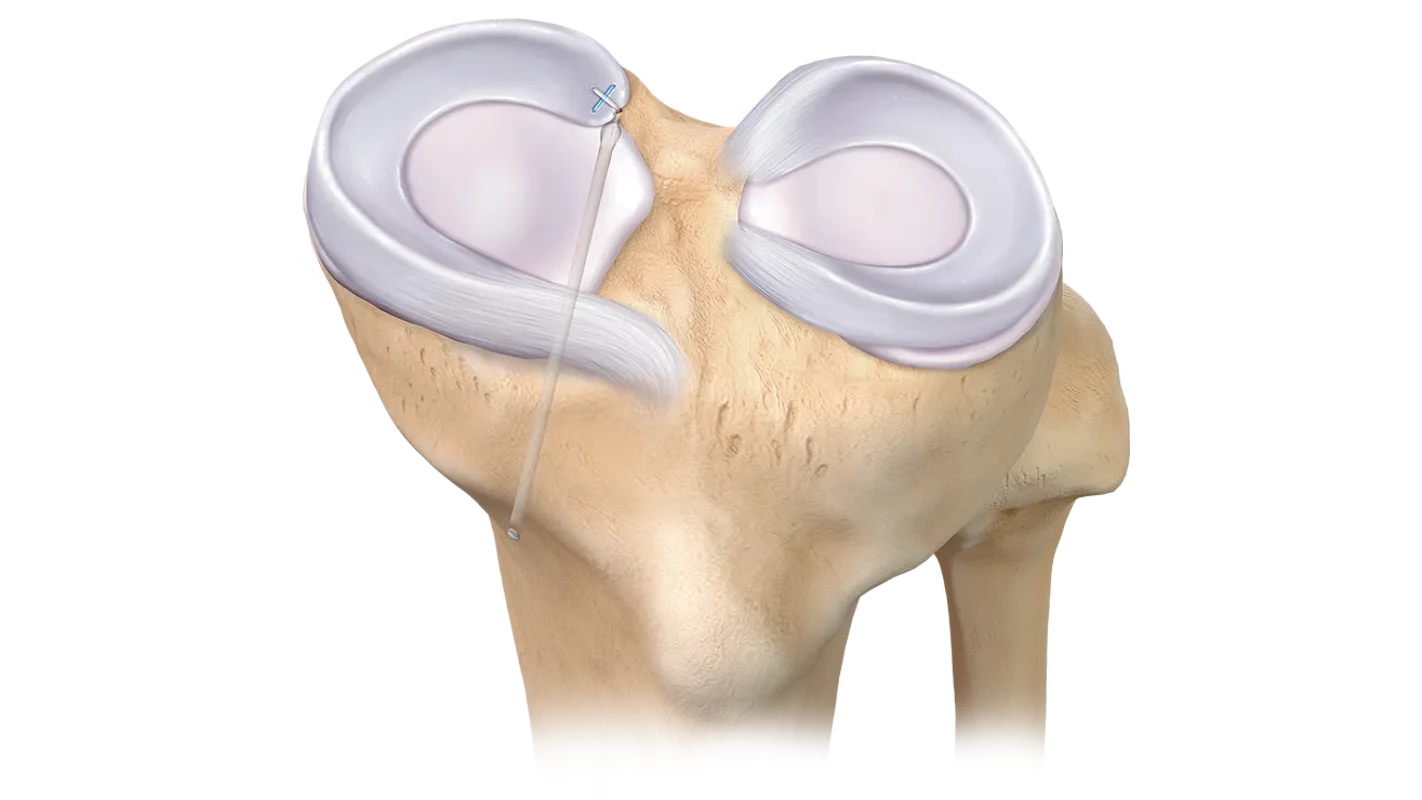

- Suturas meniscales